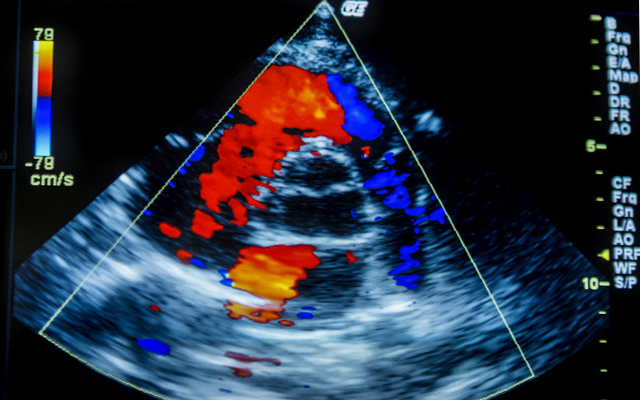

Діагностичне обстеження серця ультразвуковими хвилями активно використовують у кардіології. Ехокардіографія дає найточнішу інформацію про стан усієї серцево-судинної системи, функціональність і захворювання. Під час проведення процедури фахівець робить висновки про розміри серця та його працездатність. Процедура ЕХО-КГ серця дає змогу контролювати об’єм рідини в оболонці та кількість скорочень серцевих м’язів.

УЗД серця в Харкові проводять досвідчені діагности, які здатні оцінити функціональну діяльність серцевого м’яза, стан клапанів, визначити швидкість руху і напрямок кров’яних потоків. За тривалістю УЗ-дослідження серця займає не більше півгодини, а від пацієнта не потрібна додаткова підготовка